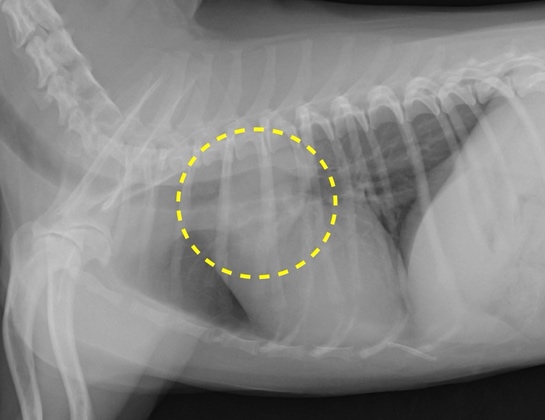

肺の腫瘍

肺癌で多く認められる症状は咳や呼吸が苦しいといった症状ですが、初期には無症状なことも多く、画像検査で偶発的に発見されることも多いです。

犬と猫の両方で最も多い原発性廃腫瘍の種類は腺癌ですが、転移性腫瘍の発生も多いです。

肺の腫瘍が限局し、転移がない場合の治療は外科手術が第一選択です。